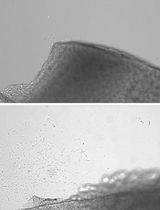

Islet transplantation in preclinical animal models can be performed in different sites such the kidney capsule, spleen, bone marrow and pancreas. This protocol describes murine islet transplantation under the kidney capsule. This is a widely accepted procedure for research purposes. Stress caused in the animals is minimal and it leads to reliable and reproducible results.

Many alternative sites for islet implantation have been reported so far in small animal models and the ideal site must be selected according to the technical advantages of the procedure to be used and for the purpose of the experiments. Bearing in mind that the kidney capsule is an extravascular site and it is not immunoprotected, pancreatic islet transplantation under the kidney capsule remains a surgical procedure with low mortality rates leading to hyperglycemia reversion within a few days. In addition, transplantation under the kidney capsule allows histological studies and formal demonstration of islet function (Cantarelli and Piemonti, 2011; Elisa Cantarelli et al., 2013).